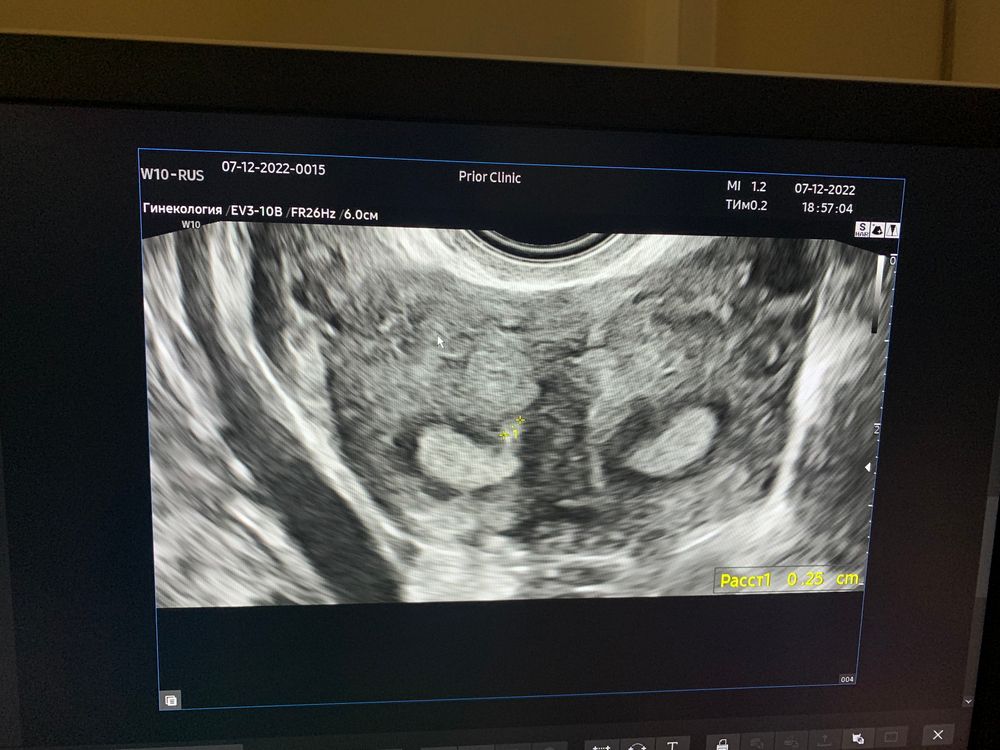

Прикрепляю Вам свое узи тут четко видно форму матки (почти полное удвоение)